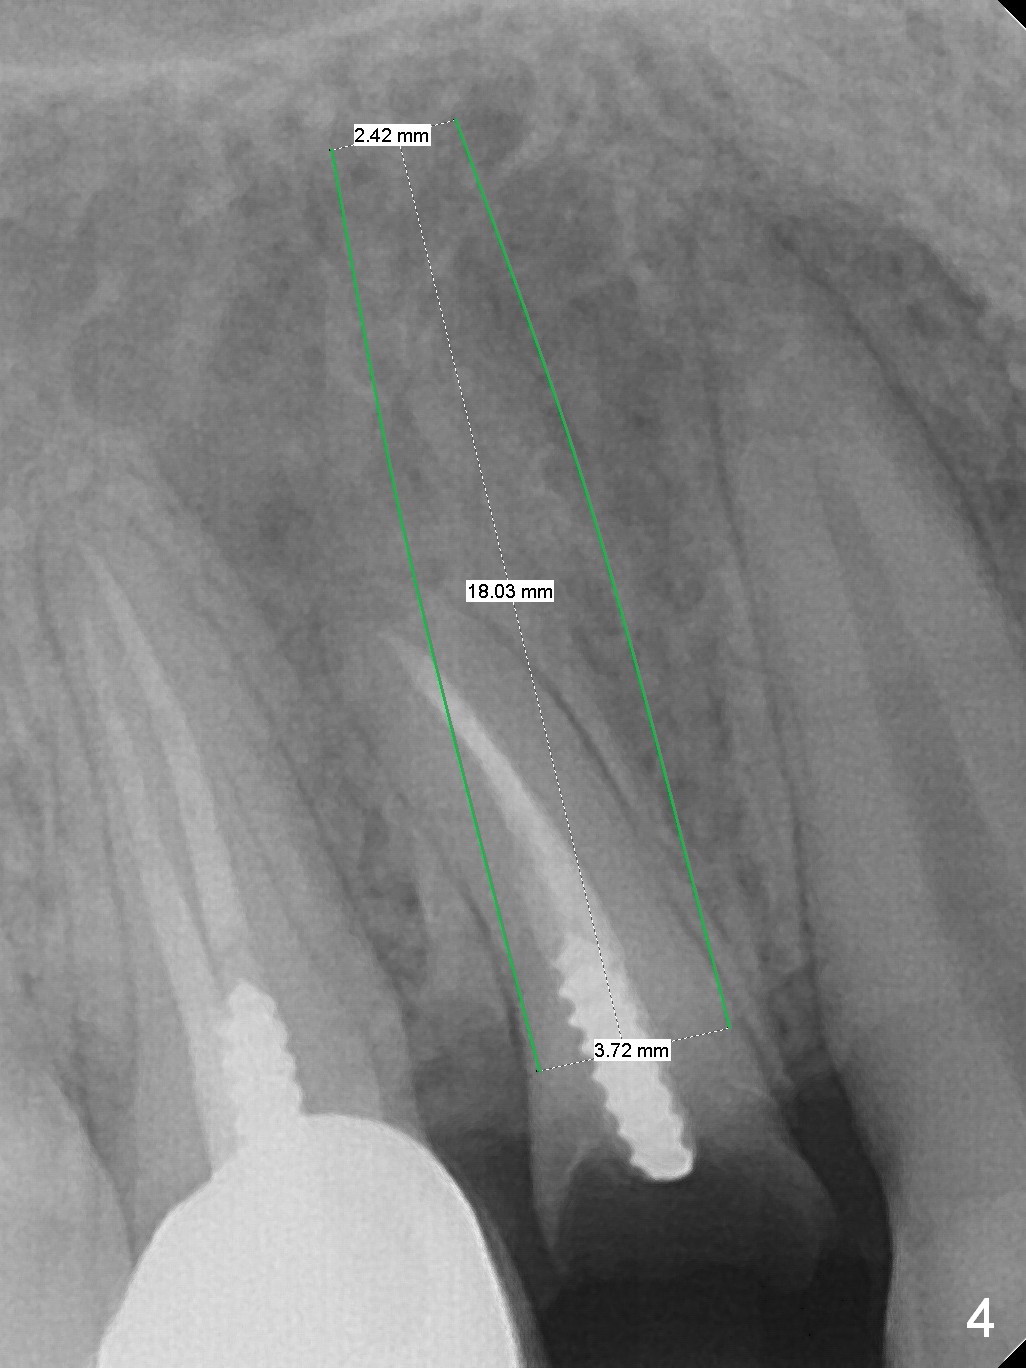

A 34-year-old man (smoker, half a pack a day) has residual root at #5 (Fig.1) with large periapical radiolucency (Fig.2 red dashed line).  Since the root curves distally (Fig.3 black area, Clindamycin), osteotomy will be established in the mesial wall (red long arrow).  A 3.8x16 or 18 mm implant is to be placed for primary stability (Fig.4).  To reduce periimplantitis associated with smoking, place the implant deep.  The implant appears to have better surface treatment.  Pack sufficient bone graft and membrane.  Immediate provisional should have good seal.  To place the implant deep, osteotomy will be attempted with a long 1.5 mm pilot drill (PA), followed by 2 mm one with extension and 3.0x18 mm drill.